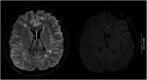

Methods: We assessed 38 adults with AT (age range 18-55 years) including 15 classic and 23 variant AT, evaluated by two independent assessors. WMHs were quantified on T2-fluid attenuated inversion recovery images using the semiquantitative modified Scheltens and Fazekas scales and CMB on susceptibility-weighted imaging and T2*-weighted gradient echo sequences using the Brain Observer MicroBleed Scale.

Results: CMBs were more frequently found in classic AT compared with variant AT (66.7% vs 5.9%) predominantly in cortical and subcortical regions. WMHs were seen in 25 (73.5%) probands and CMBs in 9 (31.0%). The burden of WMHs increased with age, and WMHs were focused in periventricular and deep white matter regions. WMHs were more frequently seen in variant than classic AT.